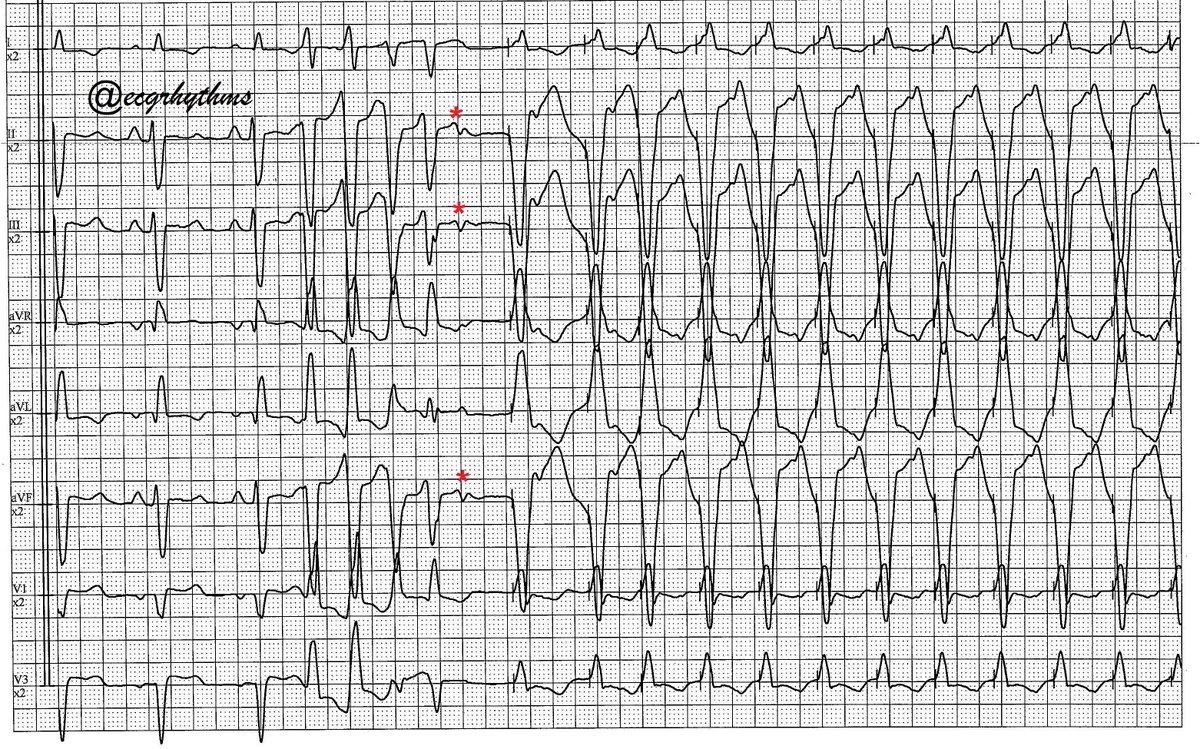

121525 From the archives/Sent by a friend It is my first time to see this phenomenal ECG - PMT (terminating) > SVT (I 🤔 looked like AVNRT). BBB is baseline. … or there is different terminology for this… I wonder. Have you seen this in the wild or in your lab?